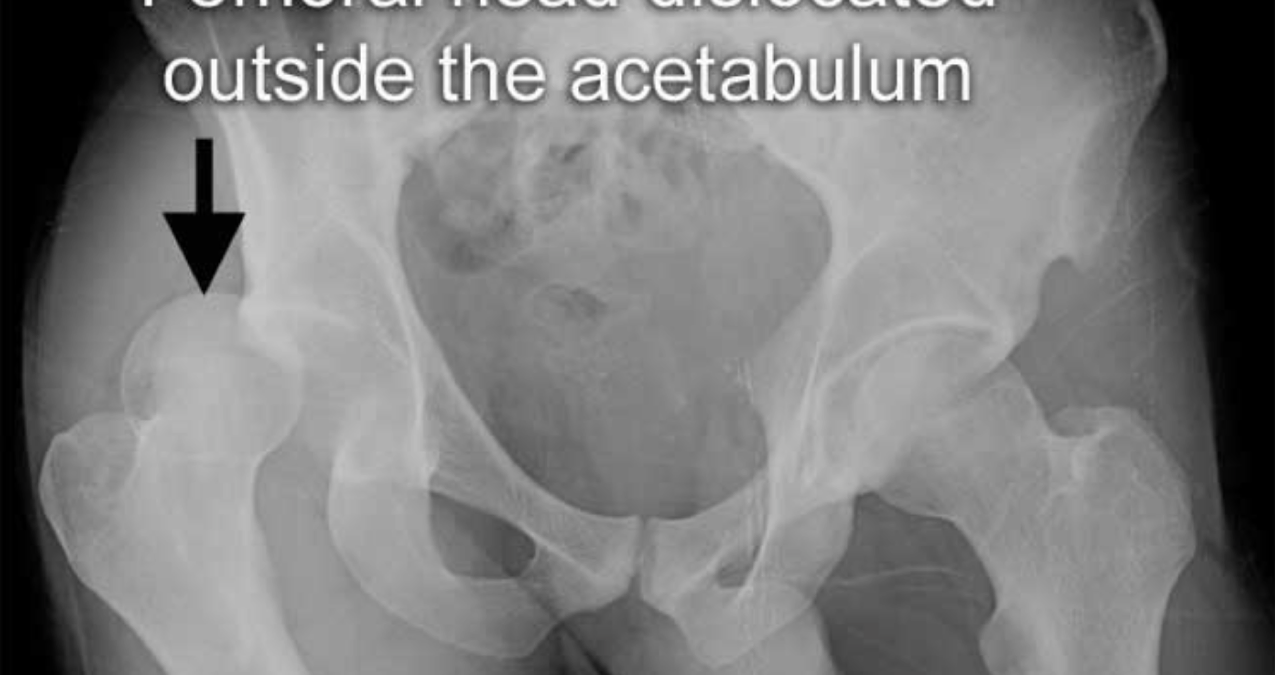

What does this radiograph show?

Hip dislocation